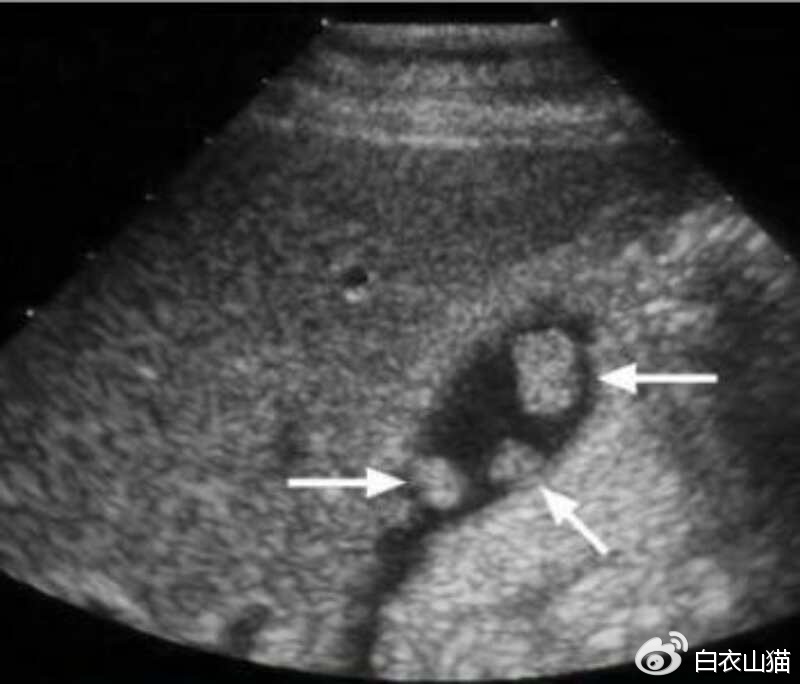

胆囊息肉的最重要检查,也是首选的检查:腹部B超。B超对人无害,又便宜。

箭头所指就是胆囊息肉

B超检查中最重要的依据是息肉大小。

息肉的B超表现有: 胆囊壁有强或稍强回声光团,其后无声影, 声像具体表现不会随着患者体位的改变 而发生移动现象。